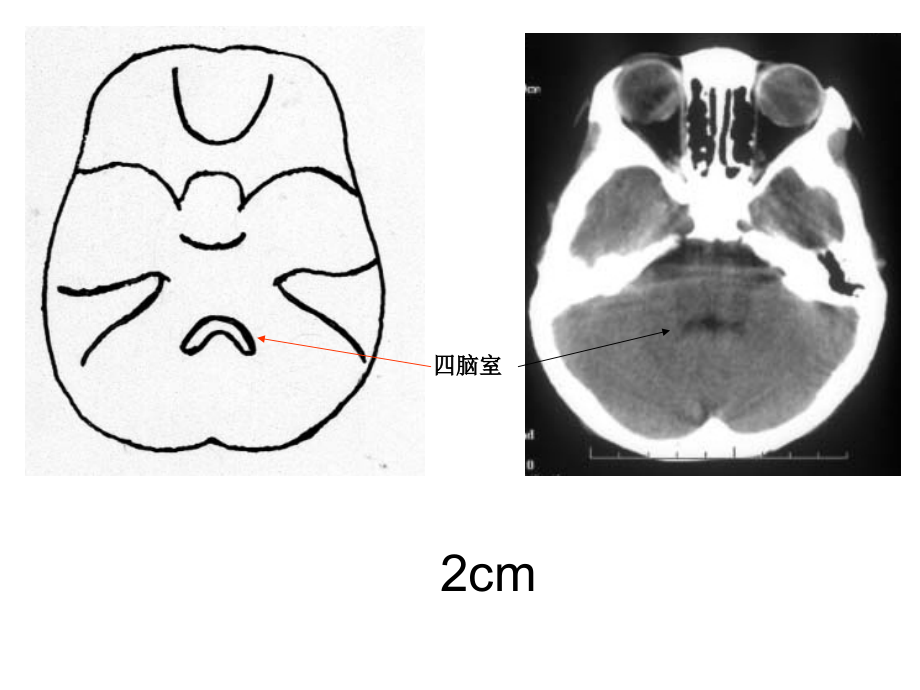

单击此处编辑母版标题样式,单击此处编辑母版文本样式,第二级,第三级,第四级,第五级,*,*,*,四脑室,2cm,鞍上池,环池,3cm,三脑室,四叠体池,4cm,侧脑室前角,侧脑室三角区及后角,大脑大静脉池,小脑上池,外侧裂池,三脑室,5cm,尾状核,豆状核,屏状核,丘 脑,豆状核:苍白球(内)、,壳核(外),基底节区:尾状核、,豆状核,5cm,基底节区结构,基底节(Basal ganglia)(又称基底神经节)是指从胚胎端脑神经节小丘发育而来的神经核团,是大脑的中心灰质核团,包括杏仁核、纹状体和屏状核。纹状体又分为:尾状核和豆状核,豆状核又可分为:壳核和苍白球。壳核和尾状核合称为新纹状体,苍白球为旧纹状体。壳核是高血压脑出血好发部位。,基底节区,杏仁核 纹状体 屏状核,尾状核 豆状核,壳核 苍白球,新纹状体 旧纹状体,侧脑室体部,6cm,